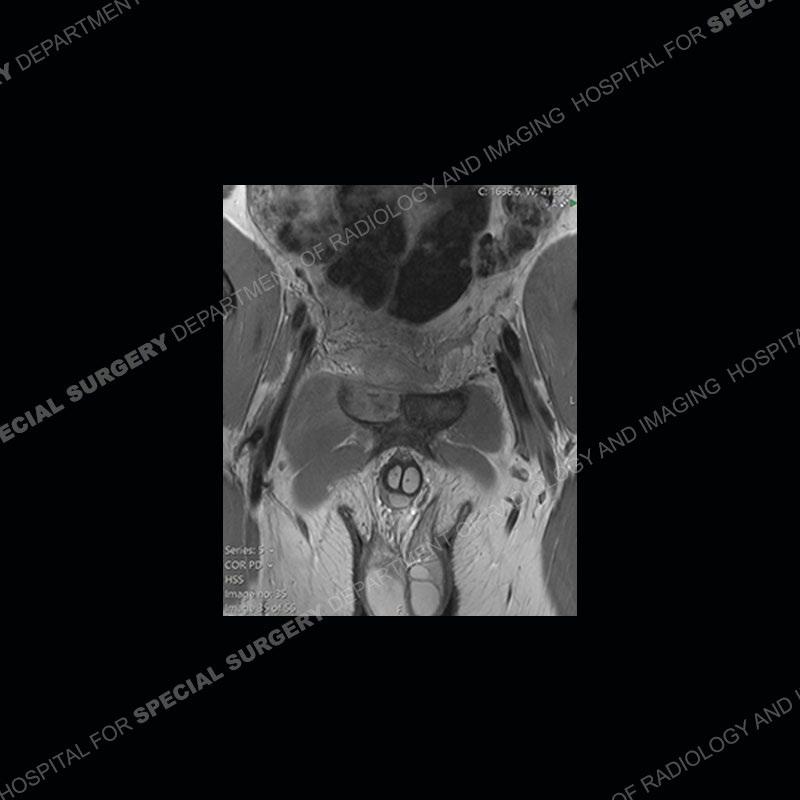

Radiographs did not demonstrate any clear abnormality. The MRI shows markedly abnormal signal of the right superior pubic ramus and abnormal signal/”mass” extending into the adjacent soft tissue. The inferior articular surface of the ramus showed what was thought to be bony destruction. CT examination shows a destructive process of the right superior pubic ramus.

Subsequent MRI in a very short time interval shows markedly increased abnormality of the ramus and increased edema and “mass” of the soft tissue. Post contrast imaging shows multiple, rim enhancing collections of the soft tissue and similar albeit less conspicuous enhancing collection of the ramus.

This case was a bit surprising to all involved given that the young man is otherwise in good health and extremely active in sports. The original thought was this case was going to be an overuse injury or stress fracture. The pubic ramus with the adjacent physis acts as a metaphyseal equivalent and although not frequently thought of would be a reasonable location for infection/osteomyelitis. The first MRI was somewhat confusing as the process did not have an appearance of a stress injury or rectus adductor aponeurosis injury. The degree of edema of the bone and soft tissue together would be odd especially for a sports hernia process. Initially, the thought was of an aggressive process which could be infection or neoplastic. Particularly, the abnormal architecture of the inferior surface of the ramus looked like a destructive process.

The repeat MRI, with the marked degree of increased abnormality of the bone and soft tissue shifted the diagnosis to a high degree towards infection. Even the most aggressive of neoplasms would not have that the degree of change in a 3-day time span. The CT study was shown before the repeat MRI but actually occurred just after the repeat MRI. It helped confirm the destructive process of the ramus and particularly the abnormal architecture along the inferior margin. The patient went on to have a CT guided aspiration of one of the soft tissue collections with 4cc of purulent fluid obtained. A surgical irrigation and debridement of the bone and soft tissue was performed. A PICC line was placed and the patient is currently undergoing IV antibiotic treatment with a possible repeat irrigation and debridement.